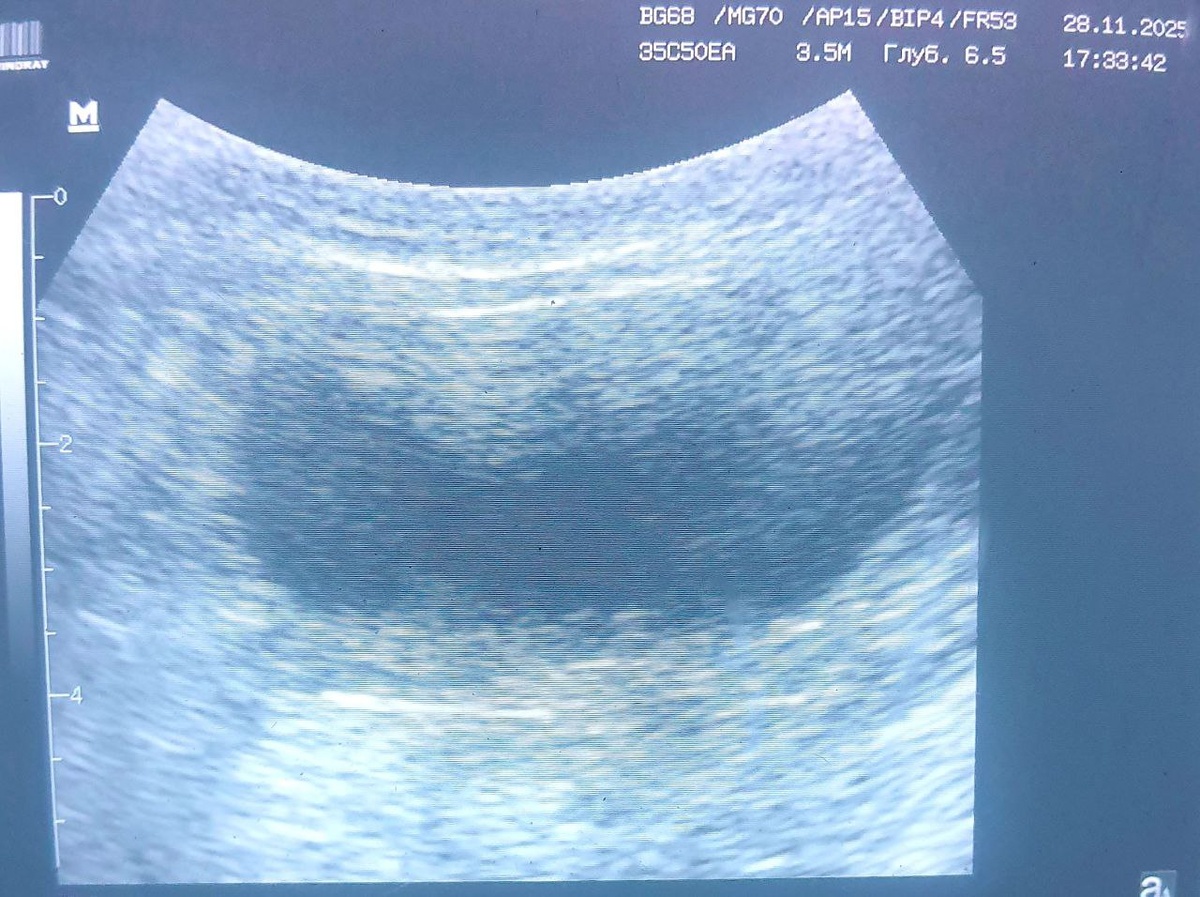

Вид мочевого пузыря при узи исследовании - хронический цистит

Вид мочевого пузыря при узи исследовании - хронический цистит. Весна и осень - время профилактических мероприятий для котов и кошек, страдающих такой патологией. Не ждем обострений!